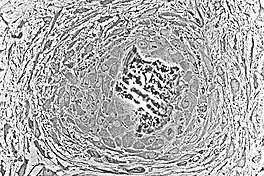

At this point, the osteoid becomes mineralized resulting in a nidus consisting of mineralized osteoid that contains osteocytes and is lined by active osteoblasts. The nidus, that began as a diffuse collection of MSCs, has developed into woven bone, the most rudimentary bone tissue.[1]

The first step in the process is the formation of bone spicules which eventually fuse with each other and become trabeculae. The periosteum is formed and bone growth continues at the surface of trabeculae. Much like spicules, the increasing growth of trabeculae result in interconnection and this network is called woven bone. Eventually, woven bone is replaced by lamellar bone.

Embryologic mesenchymal cells (MSC) condense into layers of vascularized primitive connective tissue. Certain mesenchymal cells group together, usually near or around blood vessels, and differentiate into osteogenic cells which deposit bone matrix constitutively. These aggregates of bony matrix are called bone spicules. Separate mesenchymal cells differentiate into osteoblasts, which line up along the surface of the spicule and secrete more osteoid, which increases the size of the spicule.

As the spicules continue to grow, they fuse with adjacent spicules and this results in the formation of trabeculae. When osteoblasts become trapped in the matrix they secrete, they differentiate into osteocytes. Osteoblasts continue to line up on the surface which increases the size. As growth continues, trabeculae become interconnected and trabecular bone is formed. The term primary spongiosa is also used to refer to the initial trabecular network.